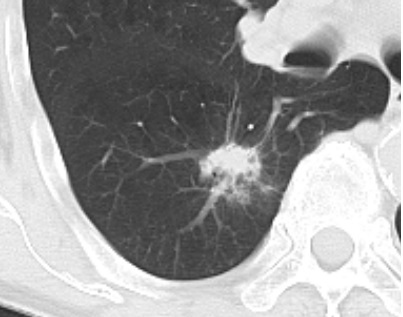

肺気腫がベースにある77歳の患者さん。

発熱、咳症状、炎症反応上昇にて来院。胸部X線に異常があり、CT施行。これを限局性肺炎ととるか、肺癌ととるか。結局厳重な経過観察となりました。